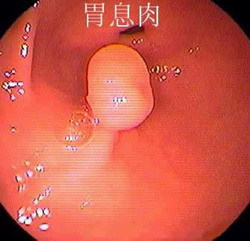

什么是胃息肉? 胃息肉(gastric polyp)是指胃黏膜局限性良性隆起病變。息肉這一名稱不表示它的病因及組織學(xué)構(gòu)造,只表示肉眼觀察到的隆起物。 胃息肉的病因: 目前病因不明。胃息肉是指起源...